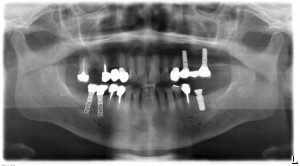

術後のレントゲンです。理想的なポジションに埋入されています。

右下の穴あきのインプラントもホローシリンダータイプと言って、初期型のITI(ストローマン)インプラントです。